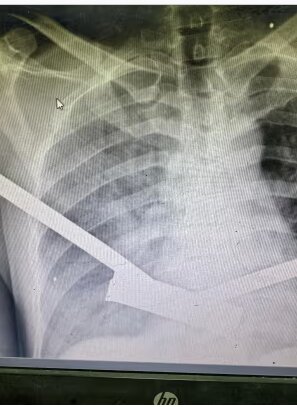

مارک پرلموتر، جراح ارتوپد از کارولینای شمالی، که در بیمارستان سیدوا کار می کرد گفت: کودکان در برابر هر گونه آسیب نافذ آسیب پذیرتر هستند، زیرا جثه کوچکتری دارند. قسمت های حیاتی آنها کوچکتر است و راحتتر از بین میرود. وقتی کودکان دچار پارگی رگهای خونی میشوند، رگهای خونی آنها آنقدر کوچک است که به سختی میتوان آنها را کنار هم قرار داد. شریان تغذیه کننده ساق، شریان فمورال، تنها به ضخامت یک رشته فرنگی در یک کودک است. خیلی خیلی کوچک است بنابراین ترمیم آن و چسباندن اندام بچه به آنها بسیار دشوار است.». تا حد زیادی شایع ترین زخم ها زخم های ورودی و خروجی یک یا دو میلی متری هستند. اشعه ایکس استخوانهای تخریبشده را نشان داد که در یک طرف آن یک سوراخ سوزنی، است و در طرف دیگر استخوانی است که به نظر میرسد یک تایر تراکتور از روی آن عبور کرده است. بچه هایی که ما آنها را عمل کردیم، اکثرشان از این مبادی ورودی و خروجی کوچک داشتند.